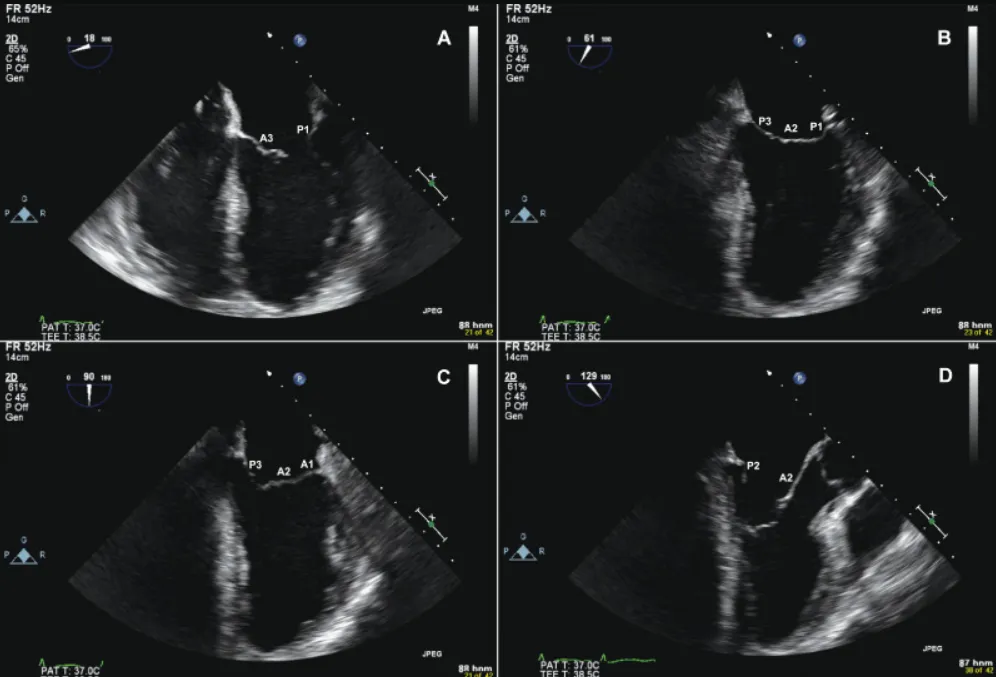

Siêu âm tim qua thực quản là kỹ thuật chẩn đoán hình ảnh, đưa đầu dò siêu âm qua miệng vào thực quản để quan sát tim. Có thể gây khó chịu nhẹ và đau họng sau đó. Thường được chỉ định khi siêu âm tim...